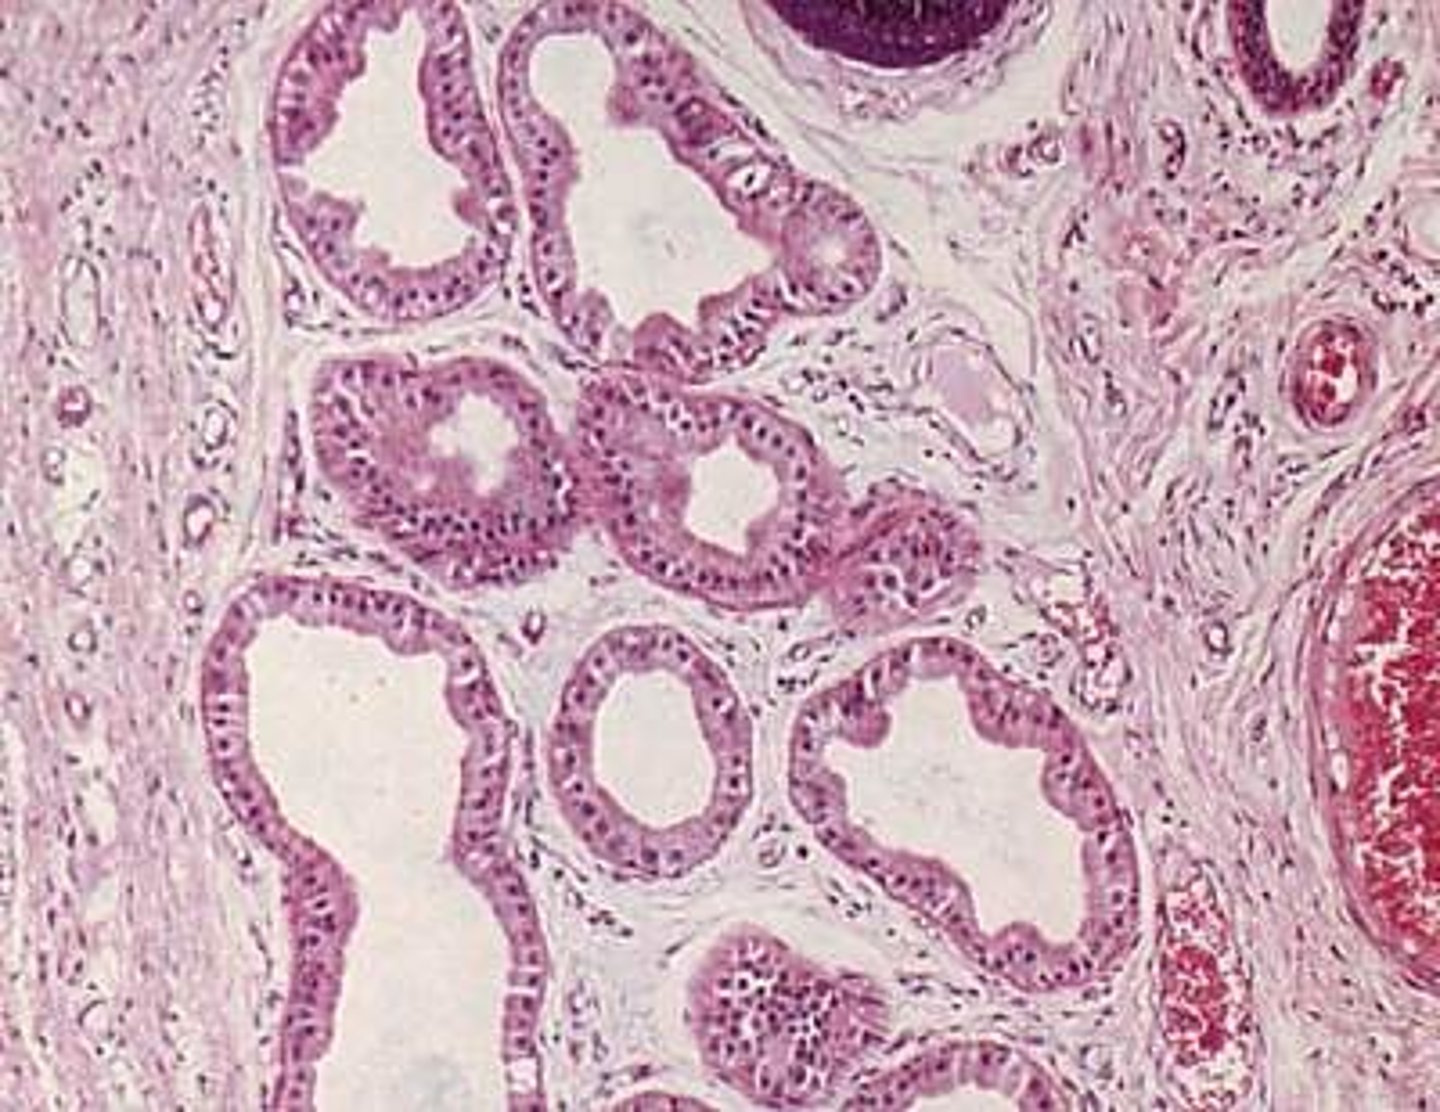

apocrine glands

Coiled structures attached to hair follicles found in the underarm and genital areas that secrete sweat.